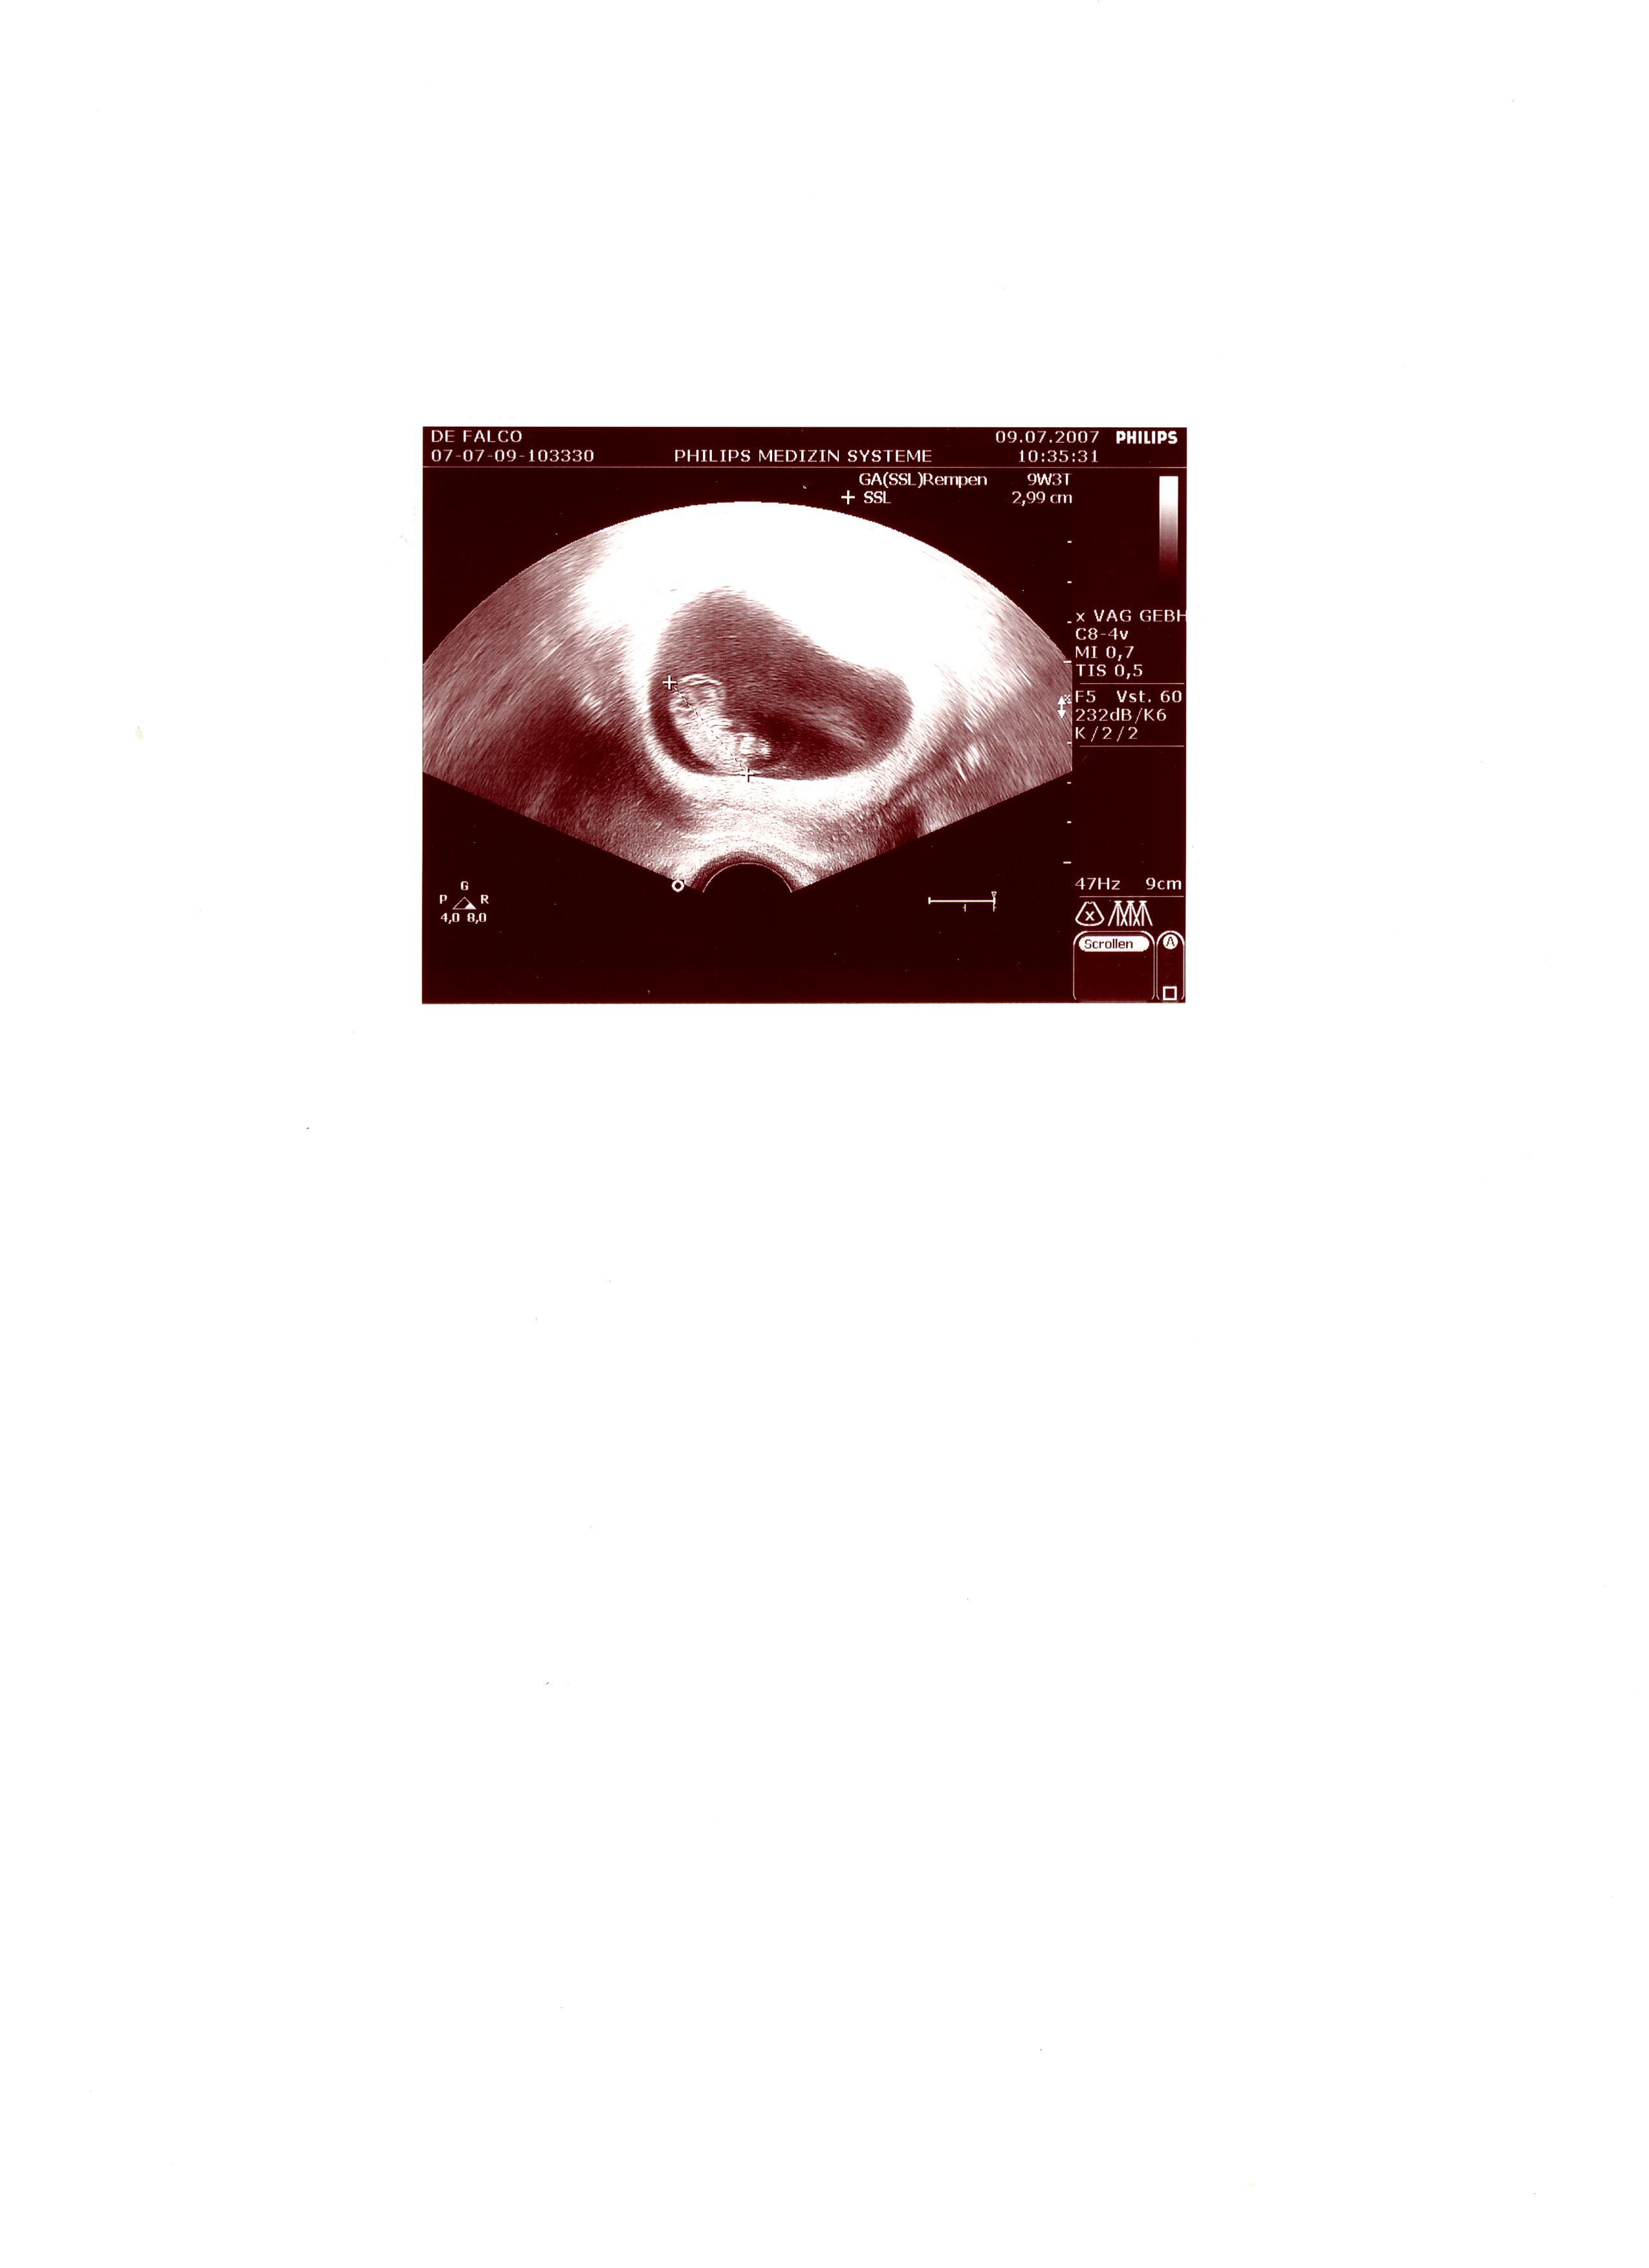

03.07. erster US, eine Fruchthöhle mit Dottersack zu sehen

10.07. das Herzlein schlägt